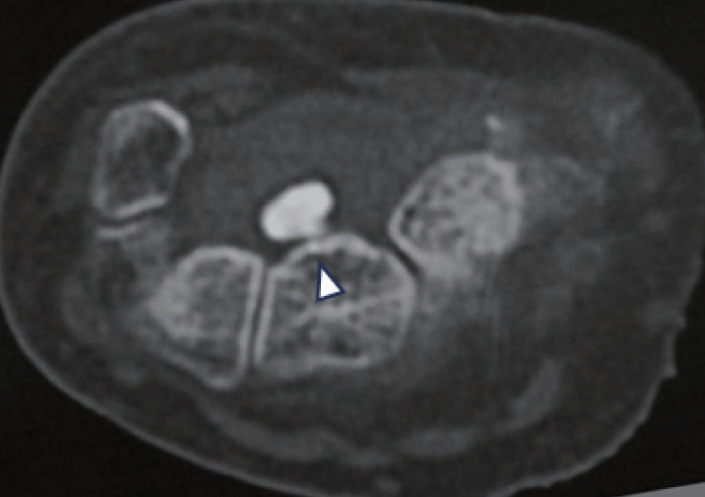

二次性の原因としては、骨折やキーンベック病などの骨性要因、手根管内腫瘤による占拠性病変、そして関節リウマチ・透析・糖尿病・アミロイドーシスなどの全身性疾患に伴う屈筋腱腱鞘滑膜炎が挙げられます。手根管内腫瘤は手根管症候群の1.8〜5%に存在し、ガングリオンや腫瘍状石灰沈着症の頻度が高く、そのほかにも腱鞘線維腫、リウマチ結節、脂肪腫、痛風結節なども報告されています。また、遺伝性圧脆弱性ニューロパチーや糖尿病性多発ニューロパチーなど神経側の脆弱性、および妊娠・浮腫・甲状腺疾患なども発症の誘因となります。

画像検査としては、まず手関節の単純X線撮影を正面・側面・手根管の3方向で行います。橈骨骨折後の変形治癒、橈骨や手根骨の変形性関節症、手根管内の石灰化といった病変を評価することができます。また、超音波検査も補助診断として有用であり、手根管症候群では手関節手掌部における正中神経の横断面積が増大し、10mm²以上を異常の基準としています。